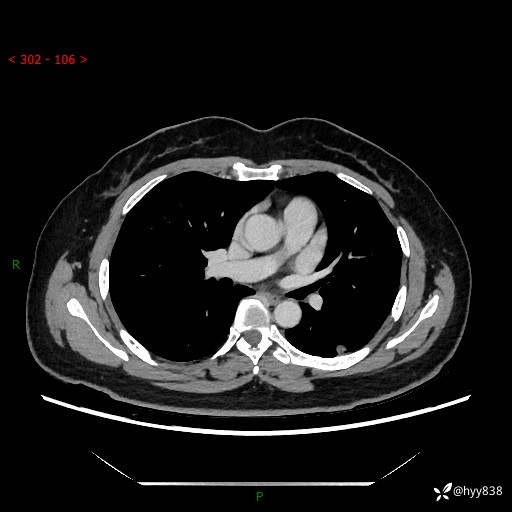

胸部CT复查+增强(2024.6)